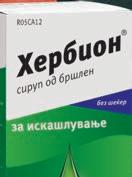

4. Изберете сируп според тип кашлица: o сува → исландски лишај o со секрет → лист од бршлен